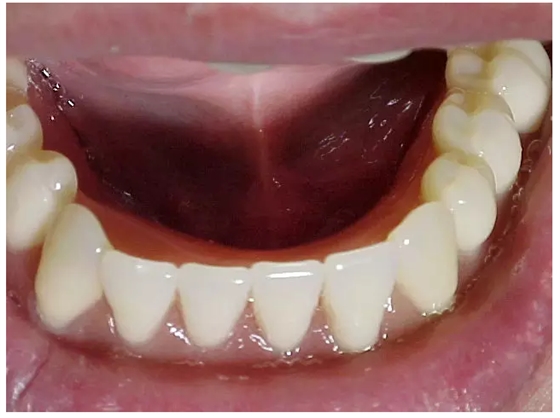

特別是有些牙槽嵴吸收嚴重的患者,此時患者的前庭顯得相當?shù)膶?,醫(yī)生應(yīng)當記錄下見到的情景,讓技師在操作時做到心中有數(shù)。